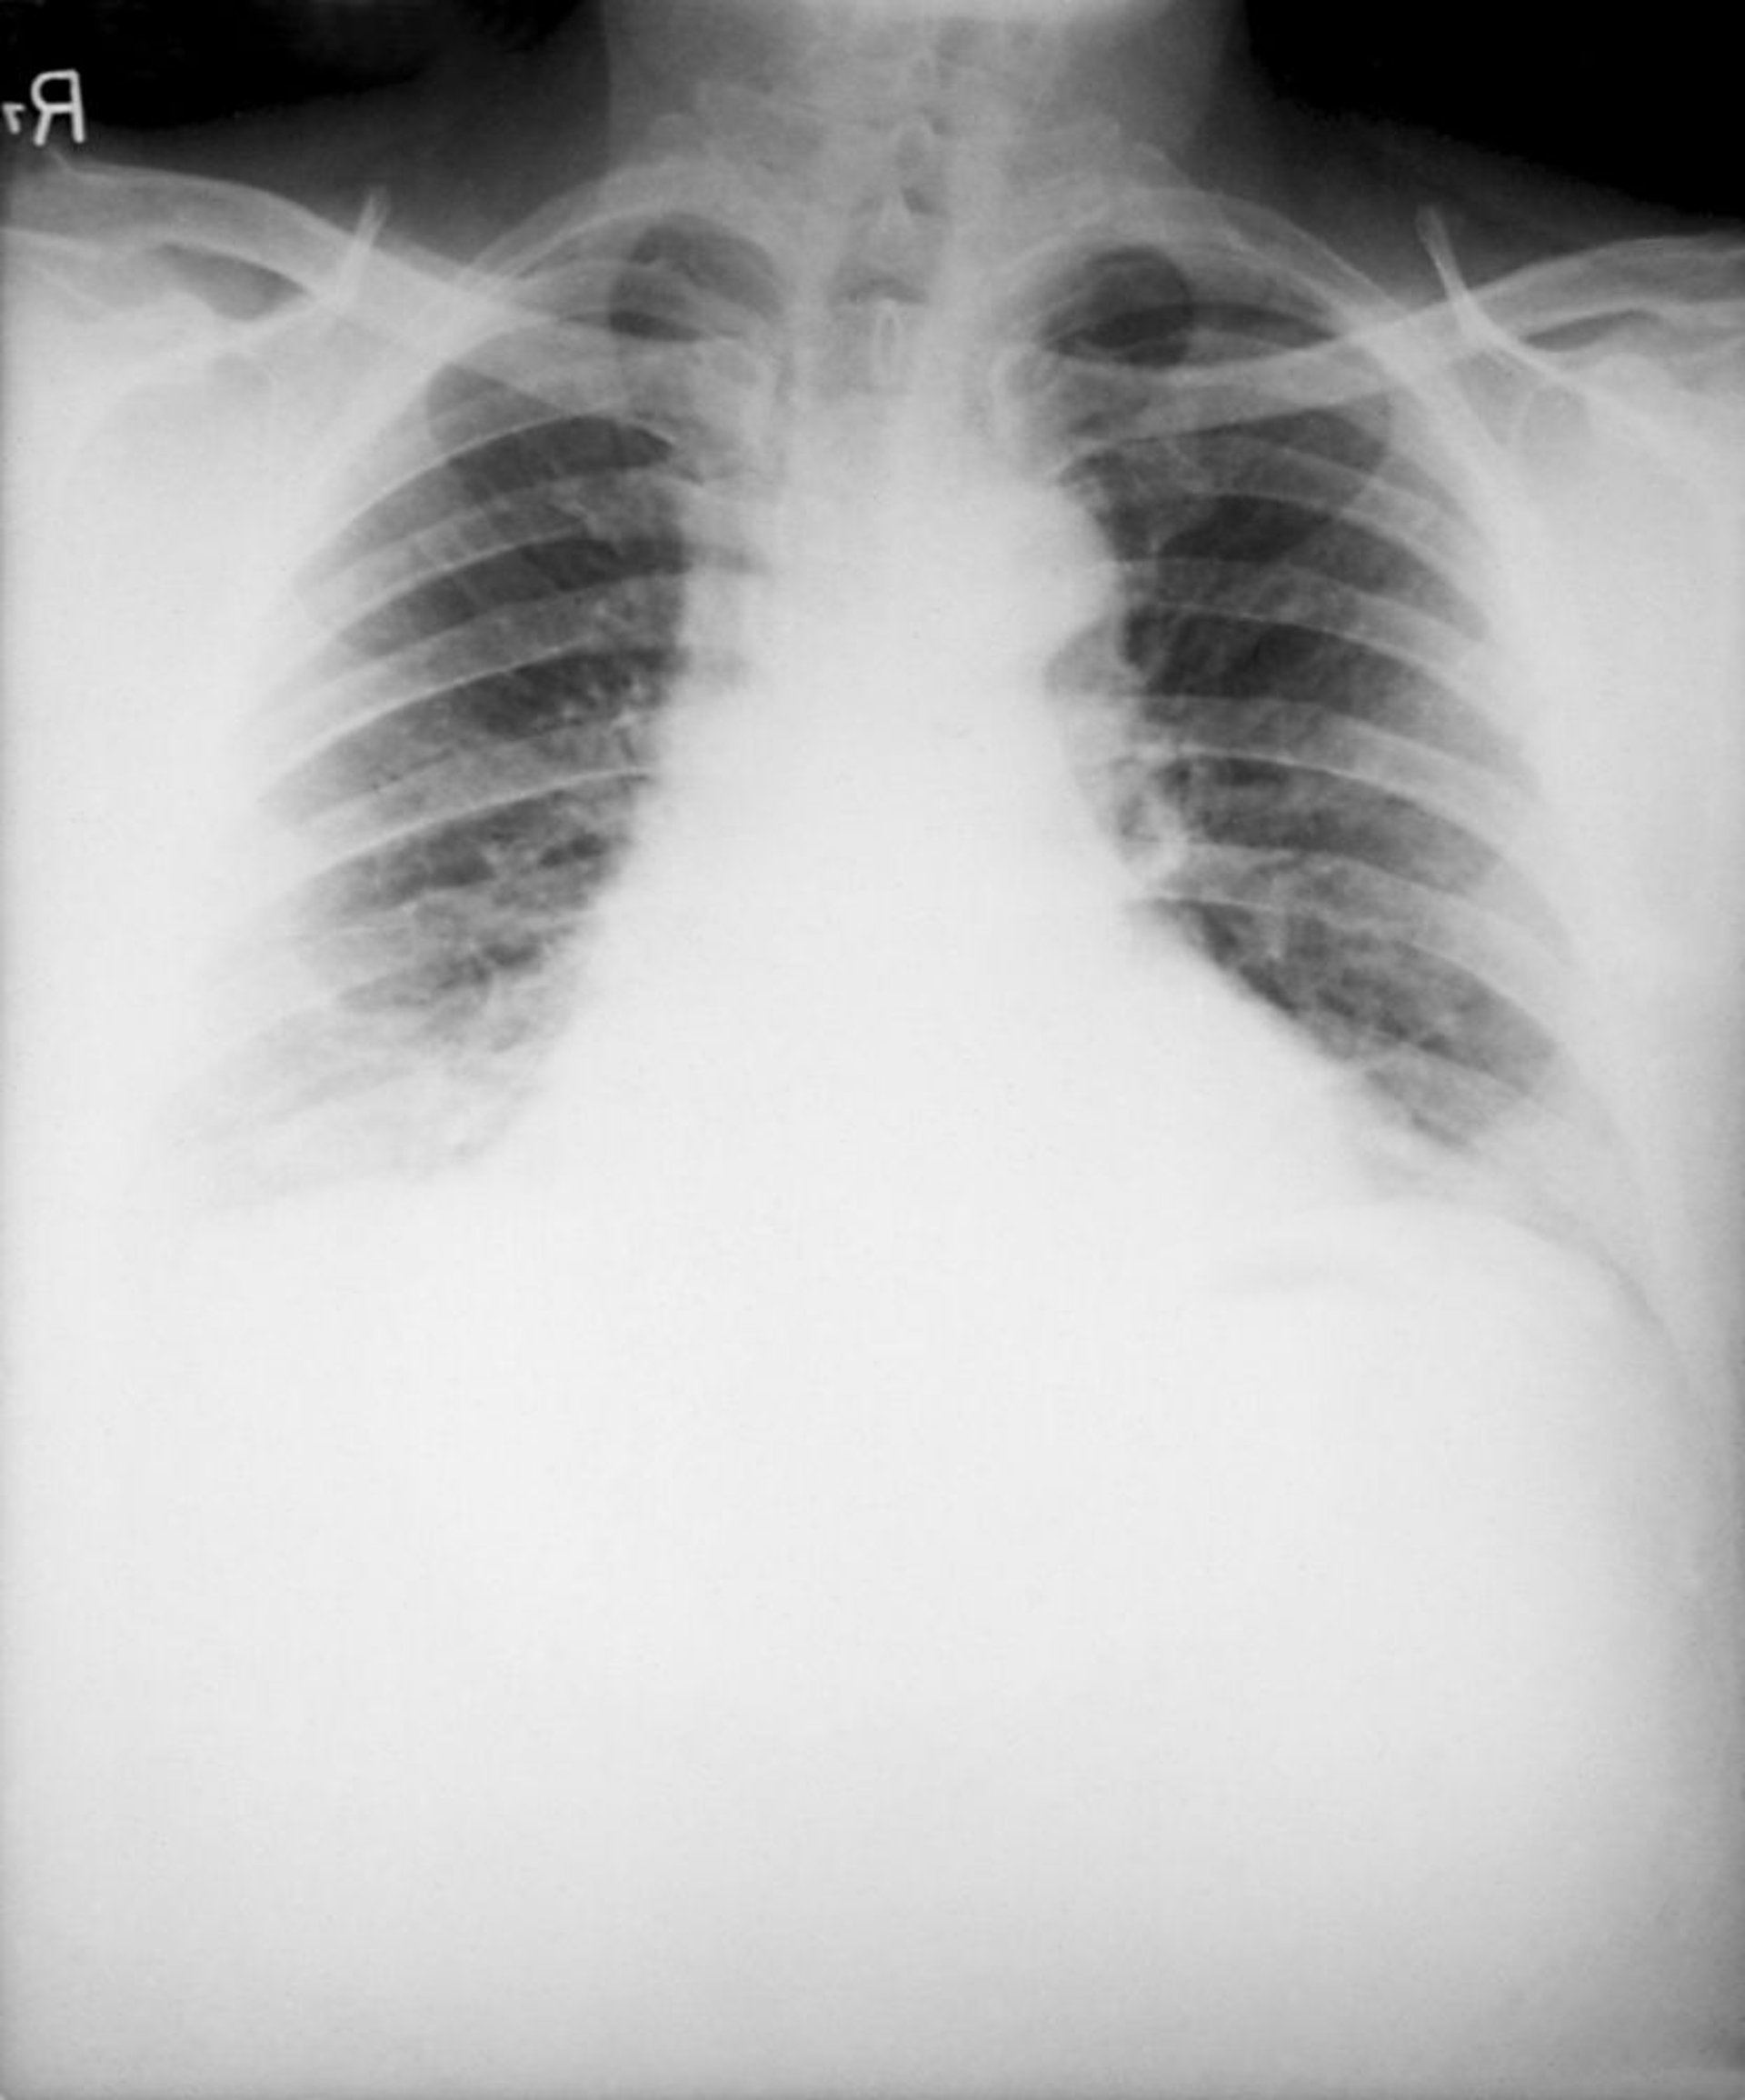

Сибирская язва (легочная форма)

К типичным признакам ингаляционной формы сибирской язвы при рентгенографическом исследовании грудной клетки относятся расширение средостения, вызванное геморрагическим некротизирующим лимфаденитом, а также двусторонним плевральным выпотом. Инфильтрация легких не характерна.

Image courtesy of the Public Health Image Library of the Centers for Disease Control and Prevention.